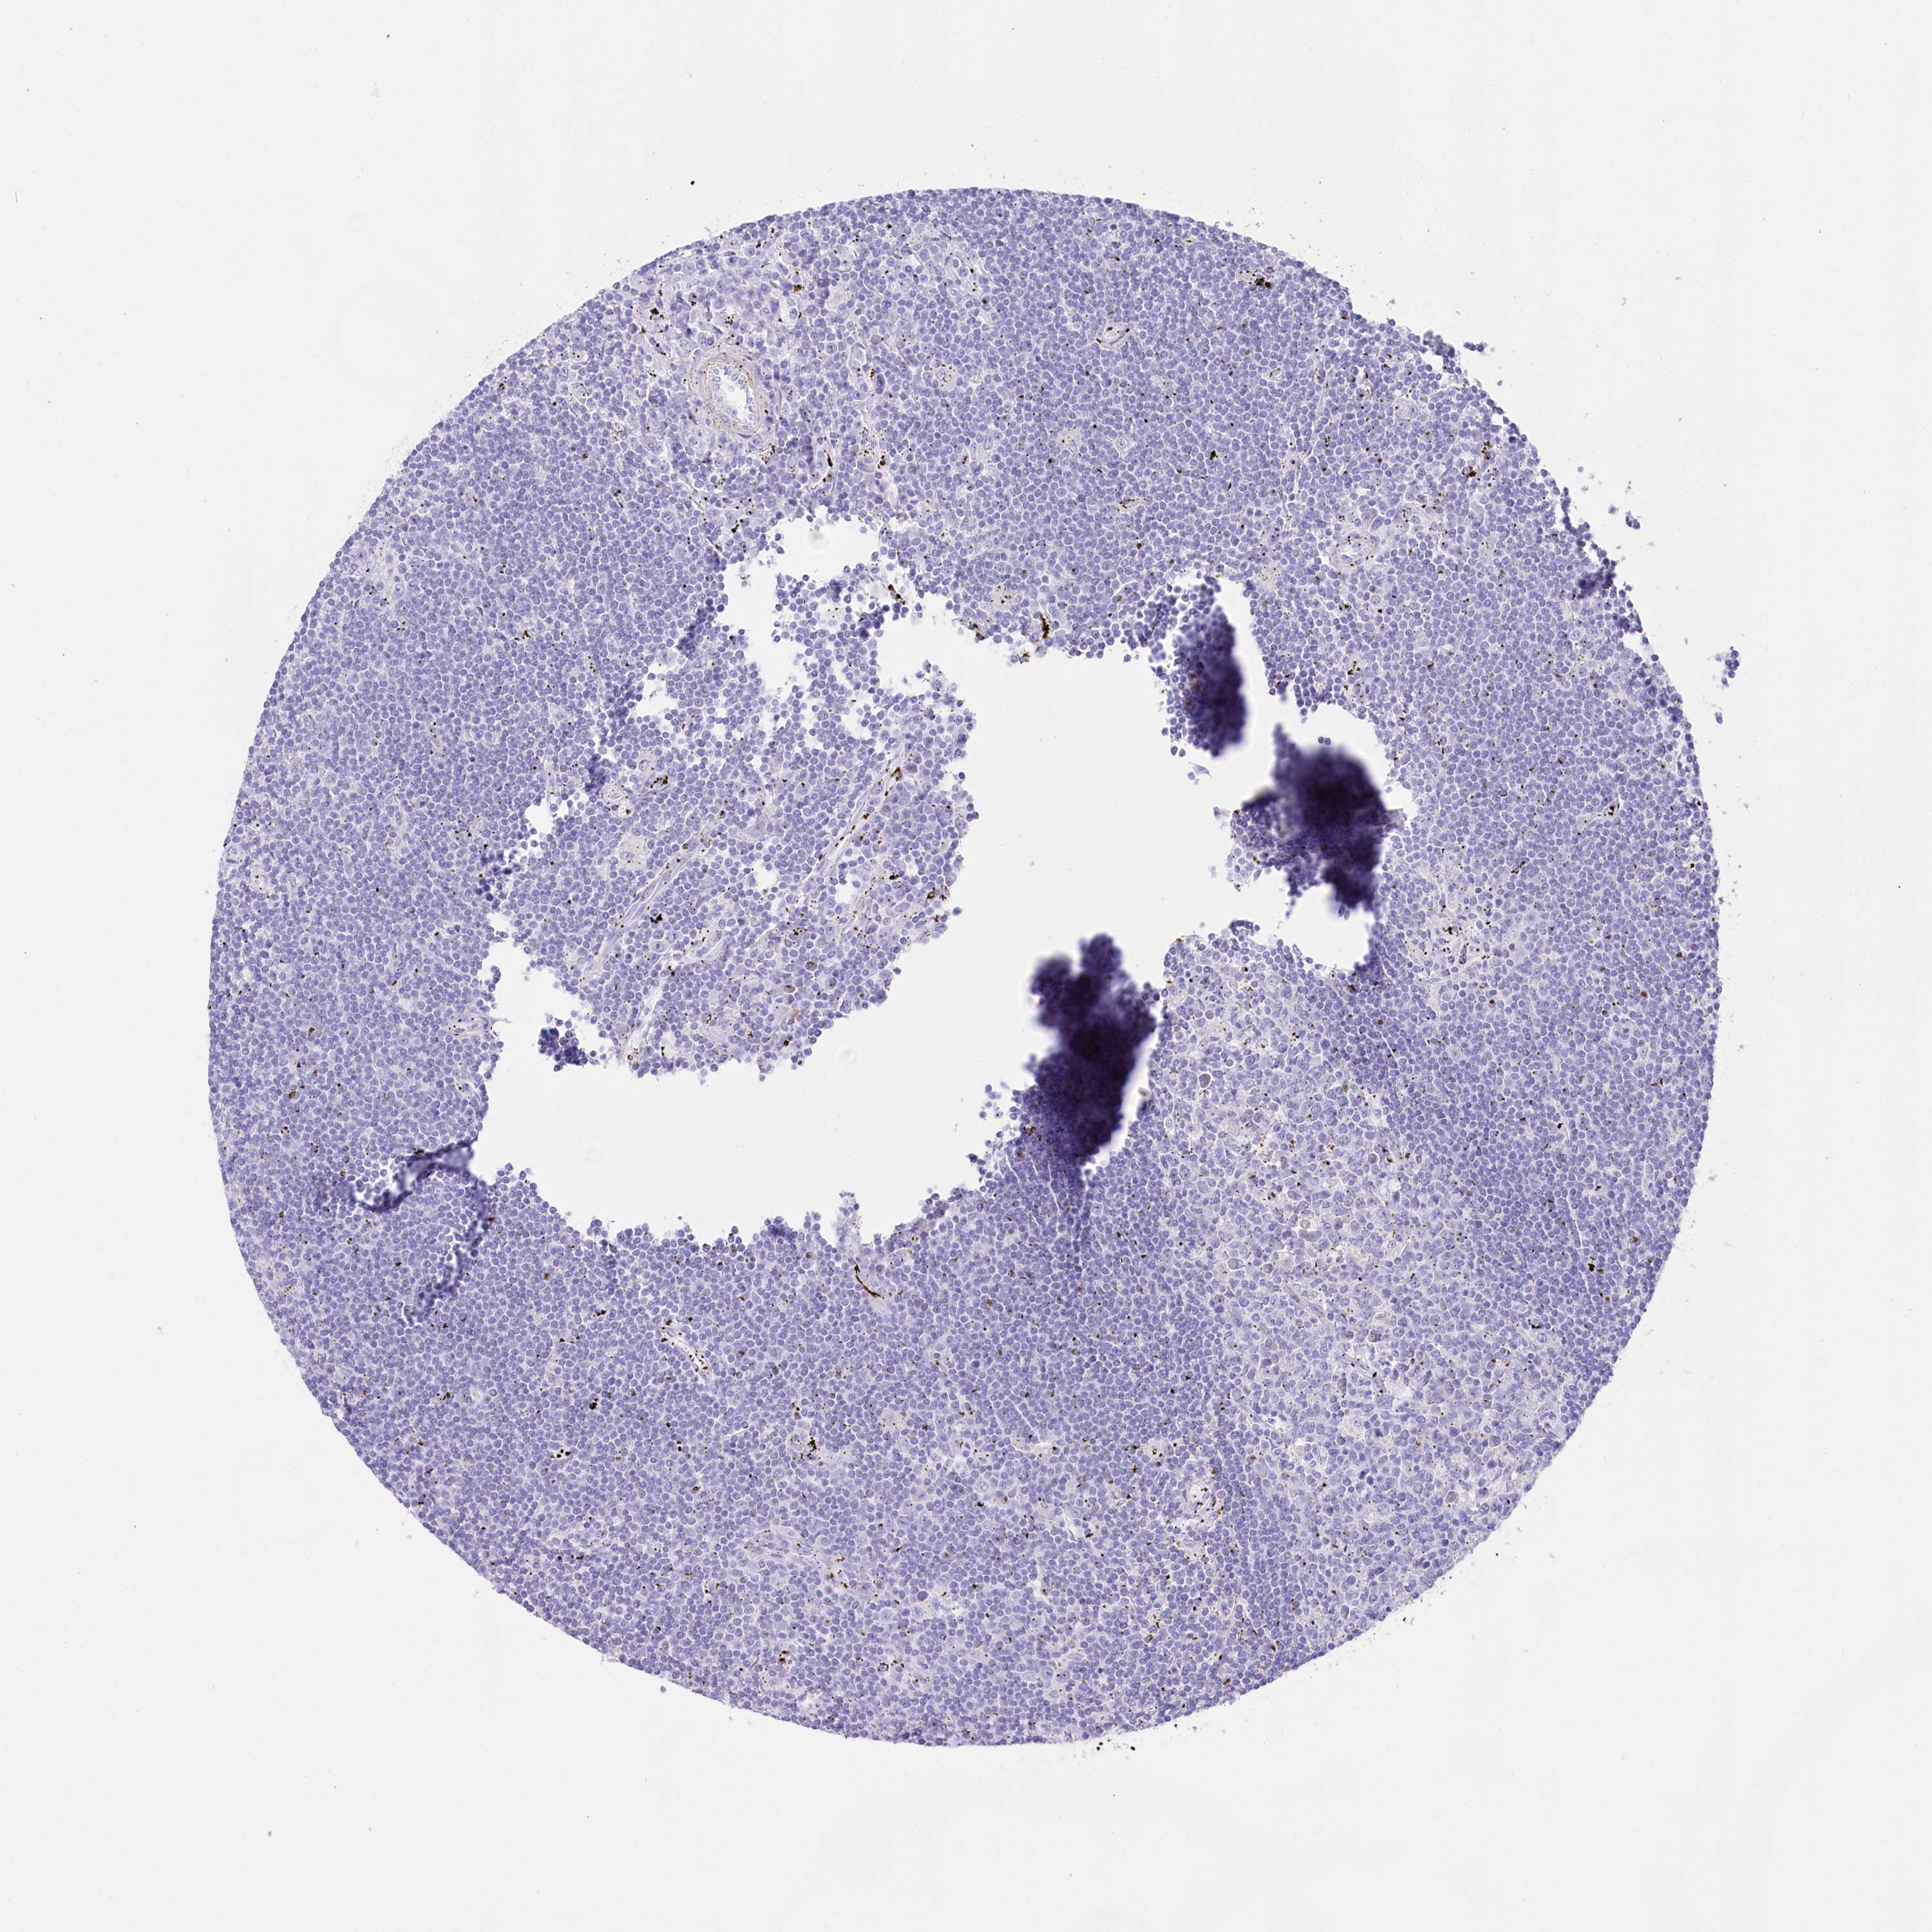

CANCER LYMPHOMA Show tissue menu

LYMPHOMA - Protein expressioni

A mouse-over function shows sample information and annotation data. Click on an image to view it in a full screen mode. Samples can be filtered based on level of antibody staining by selecting one or several of the following categories: high, medium, low and not detected. The assay and annotation is described here.

Each image is clickable and will lead to virtual microscopy that enables deeper exploration of all samples and also displays staining intensity scores, fraction scores and subcellular localization as well as patient and tissue information for each sample.

Antibody HPA035953

Hodgkin's disease, NOS

Malignant lymphoma, non-Hodgkin's type, High grade

Malignant lymphoma, non-Hodgkin's type, Low grade